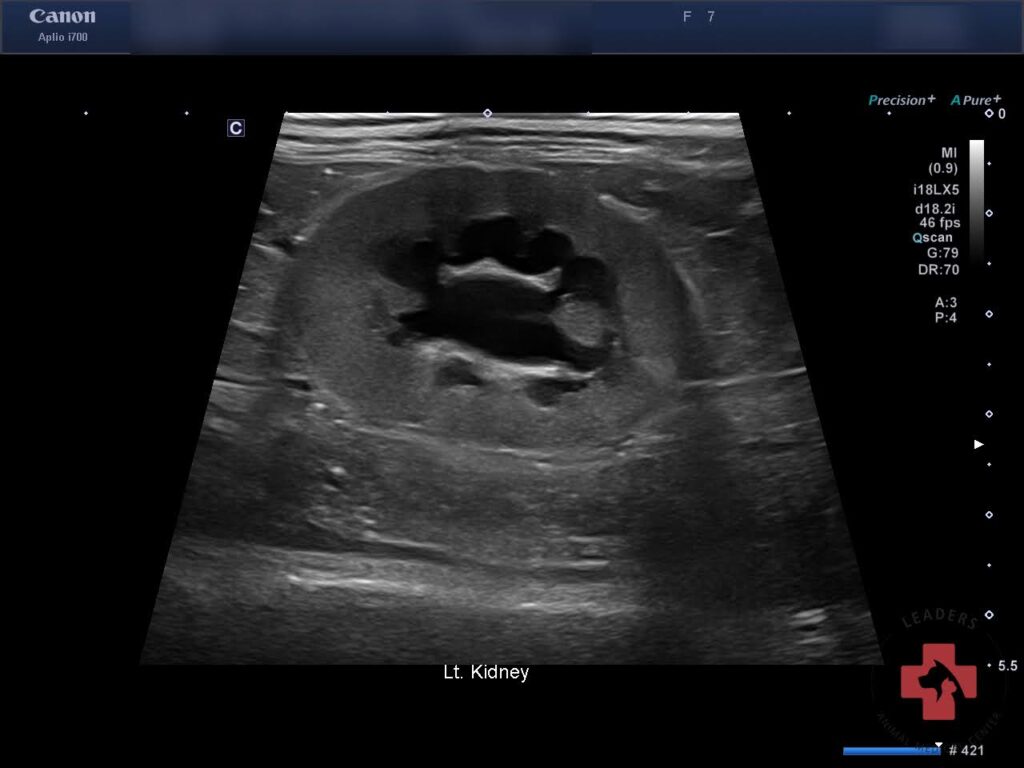

이후 실시한 본원 초음파 검사에서 양측 신장 주위 복막염 신장 피질 비후 양측 신장 신우 확장이 동반된 급성 신부전 변화가 확인되었습니다.

내원 당시 초음파검사(좌측) / 출처: 동탄리더스동물의료원